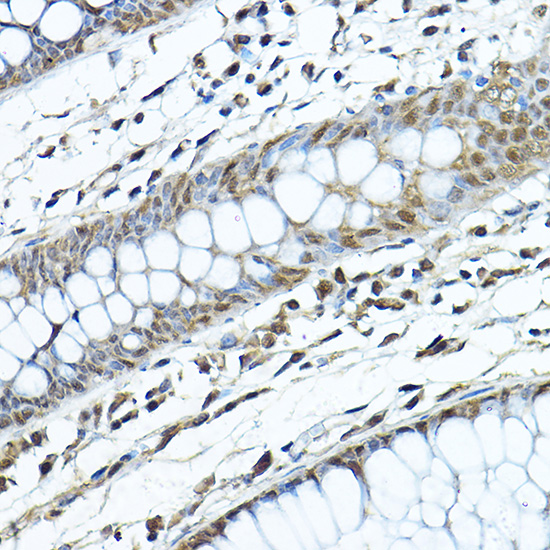

AMP-activated protein kinase (AMPK), an important serine/threonine protein kinase that plays a key role in coordinating metabolism and energy. It is the core to studying diabetes and other metabolic diseases. AMPK is expressed in a variety of metabolic-related organs and can be activated by various stimuli including cellular stress, exercise, and many hormones and substances that affect cell metabolism. AMPK proteins from different species all exist in the form of a heterotrimer complex consisting of an α-catalytic subunit, a β-regulatory subunit, and a γ-regulatory subunit.